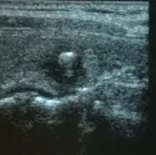

图3 甲状腺良性结节消融术后1月 20×15×10mm

图4 甲状腺良性结节消融术后3月 12×8×7mm